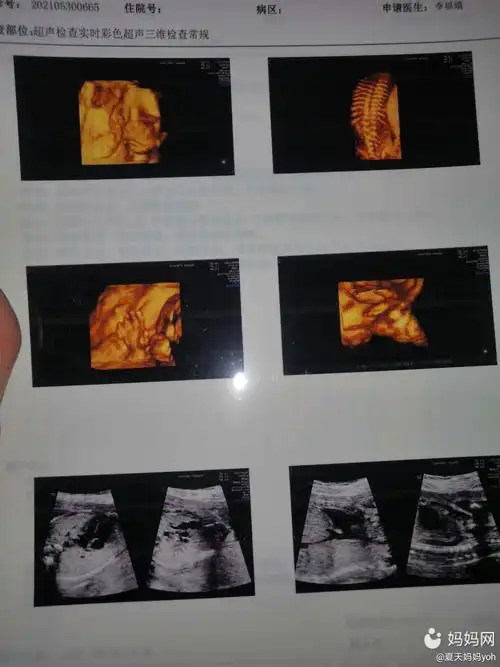

想见宝宝不用慌,四维彩超帮您忙-ge e10高端妇产彩超仪落户宁夏三院

各位妈妈们帮我看看四维照片,我家宝宝是睁着眼吗,那个黑色的是眼睛吧

四维一次通过,问医生眼睛大不大?